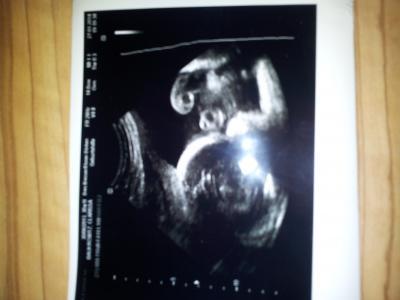

So ich war heute auch beim dritten großen Screening. Der kleine wiegt stolze 1536g und ist soweit kern gesund und zeitgemäß entwickelt. Leider hat er sich.nicht richtig zeigen wollen. Aber man erkennt trotzdem einbisschen was. :-* Und das wichtigste...er liegt jetzt auch endlich mit dem Kòpfchen nach unten.

Bild zu Auch vom 3 grossen Screening zurück :-) - Forum für April - Mamis

Hey, toll! Ich find's Wahnsinn, wie schnell sie jetzt zunehmen!! Beim Foto muss man sich wirklich erstmal orientieren. Mein "Kleiner" dreht sich im Moment auch noch munter...